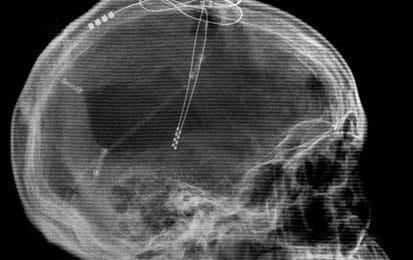

Diepe hersenstimulatie

Neurologische bewegingsstoornissen worden veroorzaakt d...